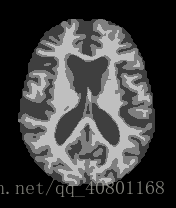

以上三张图片是成年人的大脑核磁共振图像,从左至右分别表示正常人、轻微某病、严重某病。

现在我在用深度学习(BP神经网络、CNN卷积神经网络、迁移学习等)在研究如何分类。